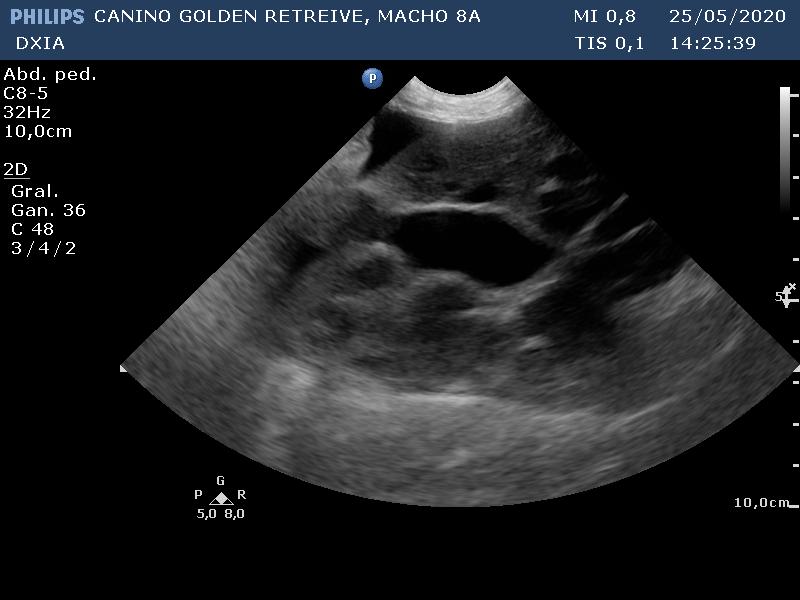

Dos imágenes obtenidas durante el estudio ecográfico:

Corte apical craneal izquierdo optimizando cámaras derechas y VT. No se detecta la existencia de Filarias adultas cardíacas ni dilatación en cámaras derechas.

Doppler de la VP donde se observa flujo laminar con velocidad máxima de la pulmonar dentro de valores normales para la especie canina.